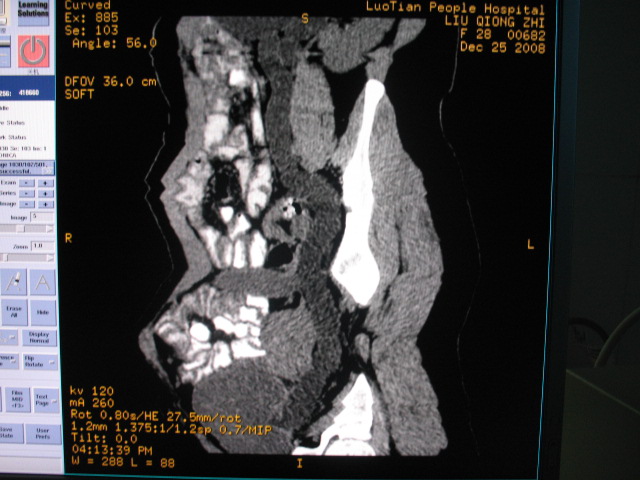

女,28岁,自觉腹部包块一年余

左侧为扩张的输尿管,一直延续到膀胱,那么它的上端应该是扩张的肾盂,但是在他的下方我们看到一个比较正常的肾,所以考虑左侧重复肾盂输尿管畸形。

考虑左侧双肾盂双输尿管畸形,其中一输尿管末端梗阻(不排除异位开口可能)并相应之肾盂及输尿管明显扩张积水。

术后证实是左侧双肾盂双输尿管畸形,巨输尿管巨肾盂症